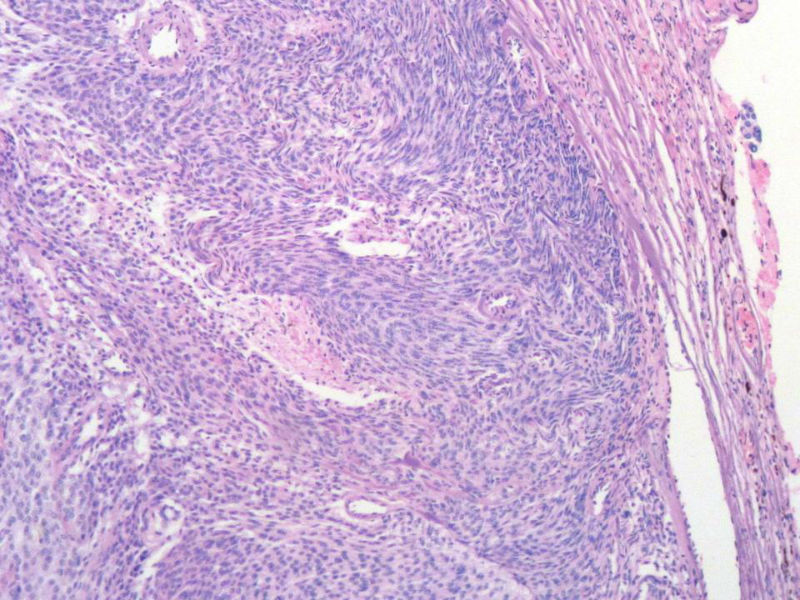

女,64岁,头晕半月,CT检查颅内左颞叶占位,侵犯颅骨和颞肌,手术切除肿物。肉眼,灰白色结节状肿物,3X3X2厘米,边界不清,切面灰黄色,质软。

特别提示:手术前曾做过介入肿瘤栓塞。镜下核分裂15/HP。脑左颞部占位图1

恶性脑膜瘤,有肌肉和骨的侵犯。

梭形细胞与上皮样漩涡状结构,富于细胞,见个别沙砾体,并见肿瘤性坏死。颅骨及其横纹肌等软组织内见肿瘤呈侵袭性生长。但细胞异型性不是很大。鉴别:

1)恶性脑膜瘤

2)非典型性脑膜瘤

由于非典型性脑膜瘤也可以发生地图状坏死,甚至侵袭性生长。需要计数核分裂数/10HPF,以资鉴别诊断。